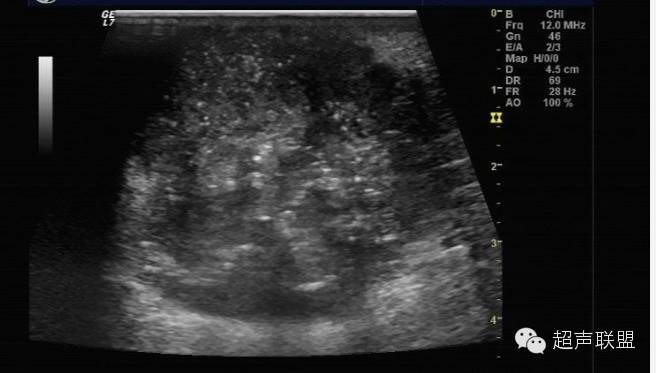

谐波成像是利用探头超声波的二次谐波成像。该技术可有效地抑制超声混响效应及其它近场噪声,但可能会限制穿透深度而导致分辨率下降,除非运用更新的宽带谐波成像技术。如图3所示液态肿块的内部回声在谐波影像中有所下降。

谐波成像减少了通常乳腺超声中可能出现的复杂液态和固态肿块的数目,同时提高了鉴定肿块为固态还是液态的准确性。该项技术也可能更清晰地定义病变边界——一个区分良性和恶性的重要特征。